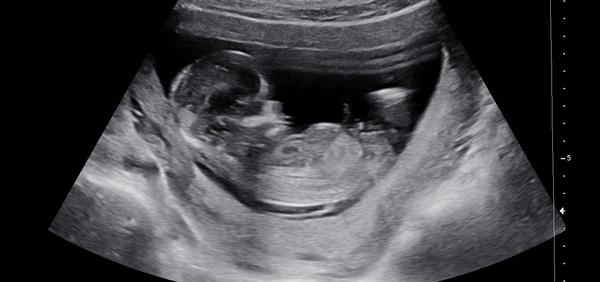

Dokáže lékař odhadnout pohlaví v 13. týdnu?

Ahoj všichni! Doktor mi dnes ve 13. týdnu řekl, že odhaduje kluka. Hodně jsem četla, že v brzkých týdnech je to celkem nerozeznatelné. Dokáže někdo třeba porovnat se svým ultrazvukem? Popř. Trefil se doktor vám?